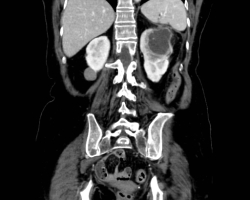

Les syndromes occlusifs, définis par l’arrêt complet du transit intestinal, regroupent quatre signes cliniques élémentaires : l’arrêt des matières et des gaz, les vomissements, la douleur et le météorisme abdominal, d’expression variable selon l’étiologie. […]